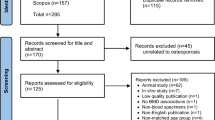

Fifty babies were enrolled: 25 with DDH and 25 age-matched non-DDH healthy controls (HC group). We collected plasma samples, laboratory parameters and conducted untargeted metabolomics profiling.

Participants

The study involved a cohort of 25 Tibetan pediatric patients diagnosed with DDH at the People’s Hospital of Tibet between January 2021 and March 2022. Inclusion in the study required a confirmed diagnosis of one of the following: (1) a complete hip joint dislocation, with no contact between the original articulating surfaces; (2) a hip joint subluxation, with partial contact maintained between the articulating surfaces; or (3) acetabular dysplasia, characterized by insufficient development of the acetabulum. The diagnosis was rendered by seasoned pediatric orthopedic specialists based on comprehensive medical evaluations, which included assessments of abnormal gait patterns such as limping or Trendelenburg gait. Physical examinations for asymmetrical gluteal folds or thigh skin creases were also conducted. Additional clinical signs considered were the pronounced elevation and lateral displacement of the greater trochanters, restricted abduction of the hip joint, and positive Ortolani, Barlow, Allis, or Galeazzi signs. Diagnostic confirmation was achieved through X-ray imaging. Cases with concurrent chronic diseases or other musculoskeletal disorders were meticulously excluded to maintain the study’s focus on isolated DDH. The control group comprised healthy Tibetan children who underwent routine health screenings at the People’s Hospital of Tibet concurrently with the study period and exhibited no abnormalities. The selection of control subjects was age and gender-matched to the case group to ensure comparability.

Fasting blood samples were collected. Centrifuge the blood at 3000 rpm for 10 min at 4 °C, then remove the supernatant and sub-package it into 1.5 mL centrifuge tubes. Finally, freeze the sample at -80 °C. The clinical data was described in Table 1.